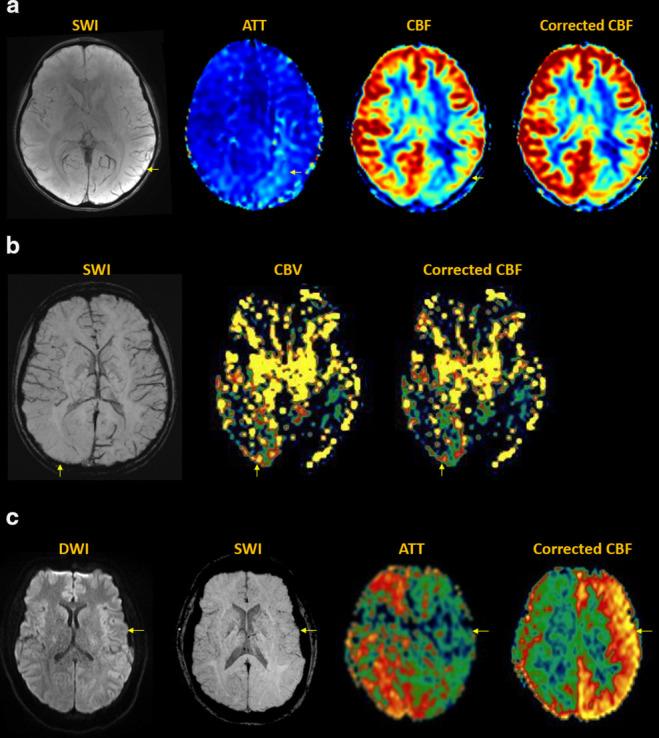

Arterial spin labeling (ASL) is a powerful noncontrast MRI technique for evaluation of cerebral blood flow (CBF). A key parameter in single-delay ASL is the choice of postlabel delay (PLD), which refers to the timing between the labeling of arterial free water and measurement of flow into the brain. Multidelay ASL (MDASL) utilizes several PLDs to improve the accuracy of CBF calculations using arterial transit time (ATT) correction. This approach is particularly helpful in situations where ATT is unknown, including young subjects and slow-flow conditions. In this article, we discuss the technical considerations for MDASL, including labeling techniques, quantitative metrics, and technical artefacts. We then provide a practical summary of key clinical applications with real-life imaging examples in the pediatric brain, including stroke, vasculopathy, hypoxic-ischemic injury, epilepsy, migraine, tumor, infection, and metabolic disease.

动脉自旋标记 (ASL) 是一种强大的非对比 MRI 技术,用于评估脑血流 (CBF)。单延迟 ASL 的一个关键参数是后标记延迟 (PLD) 的选择,它是指动脉游离水标记与脑内血流测量之间的时间间隔。多延迟 ASL (MDASL) 使用多个 PLD 利用动脉通过时间 (ATT) 校正来提高 CBF 计算的准确性。这种方法在 ATT 未知的情况下特别有帮助,包括年轻受试者和低流速情况。本文讨论了 MDASL 的技术注意事项,包括标记技术、定量指标和技术伪影。然后,我们提供了一个实用的总结,介绍了儿科大脑中的关键临床应用,包括中风、血管病变、缺氧缺血性损伤、癫痫、偏头痛、肿瘤、感染和代谢性疾病,并提供了真实的成像示例。